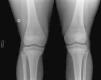

El paciente acude a urgencias tras 6 ciclos de tratamiento, por gonalgia izquierda, objetivándose en la radiografía líneas densas metafisarias paralelas a los cartílagos de crecimiento (fig. 2).

La DFO es una lesión ósea benigna, de evolución lenta, que afecta frecuentemente a los maxilares. La transformación maligna es rara. Las imágenes osteocondensantes que aparecen en los huesos tubulares y pelvis de estos pacientes, a consecuencia del tratamiento con bifosfonatos2, son similares a las líneas de Harris observadas por diversas causas en el esqueleto inmaduro3,4.

Estas líneas paralelas a las fisis, denominadas «líneas cebra», son el resultado de una detención momentánea del crecimiento, reanudándose posteriormente con deposición de hueso nuevo calcificado. Dichas líneas, reflejarían un desequilibrio temporal del recambio óseo y explicarían su aparición con la administración de cada ciclo de pamidronato4 (Fig. 2).

Característicamente, estas líneas se alejan de la fisis con el crecimiento, por lo que es posible tener el registro permanente en el hueso del número de ciclos recibidos.